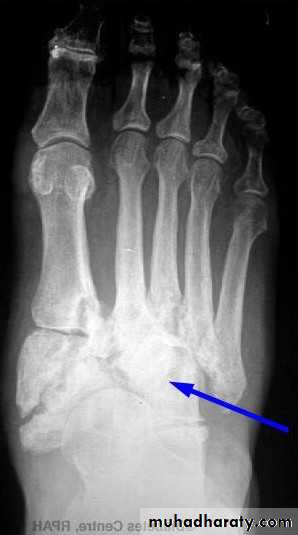

In gout ,the deposition of the urate crystals in the joint & in the adjacent bone gives arise to an arthritis which most commonly affects the metatarsophalangeal joint of the big toe .Radiological changes involving :

1.soft tissue swelling 2 . erosions 3 . usually no osteoporosis .4 . Tophi.